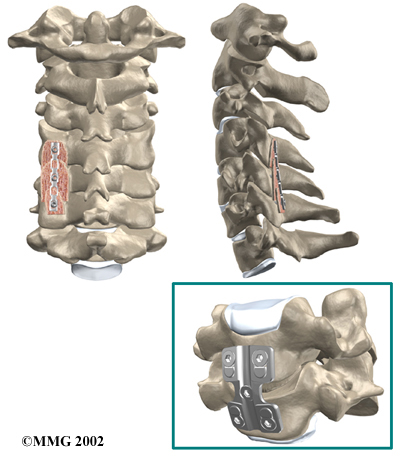

Cervical Fusion

A fusion surgery joins two or more bones into one solid bone. The purpose for doing spinal fusion is to increase the space between the vertebrae and to keep the sore joint from moving. This is usually done by placing a small block of bone graft in the space where a disc was removed. Opening up more space enlarges the neural foramen, takes pressure off the nerve roots, and eases tension on the facet joints. Cervical fusion is used to treat neck problems such as cervical radiculopathy, disc herniations, fractures, and spinal instability. There are two main types of fusion for neck problems.

- Anterior Discectomy and Fusion: Anterior discectomy and fusion is done through the front of the neck. After taking out the disc (discectomy), the disc space is filled with a small graft of bone. The bone is allowed to heal, fusing the two vertebrae into one solid bone.

Small Graft of Bone

- Posterior Fusion: In posterior fusion, the surgeon lays small grafts of bone over the back of the spine. When these bones heal together, they fuse the two vertebrae into one solid bone. Posterior fusions in the cervical spine are primarily used to treat fractures of the neck.

Posterior Fusions

The bone graft needs time to heal in order for the fusion to succeed. This requires the neck to be held still. After cervical fusion surgery, patients usually have to wear a special neck brace for several months. These neck braces are often bulky and restrictive. Recently, surgeons have begun using metal plates and screws (often referred to as instrumentation) to lock the bones in place. The instrumentation is fastened to the vertebrae, where it holds the bones still while the graft heals.

Locking the Bones in Place